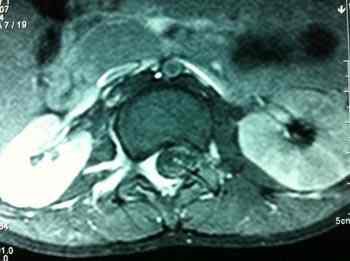

PARACLÍNICA: PL Citoquímico: Cels. 300 xc, Prot. 2196 mg/dl, Gram -, BK –, polio en heces (–), HIV (–),CNM: bloqueo